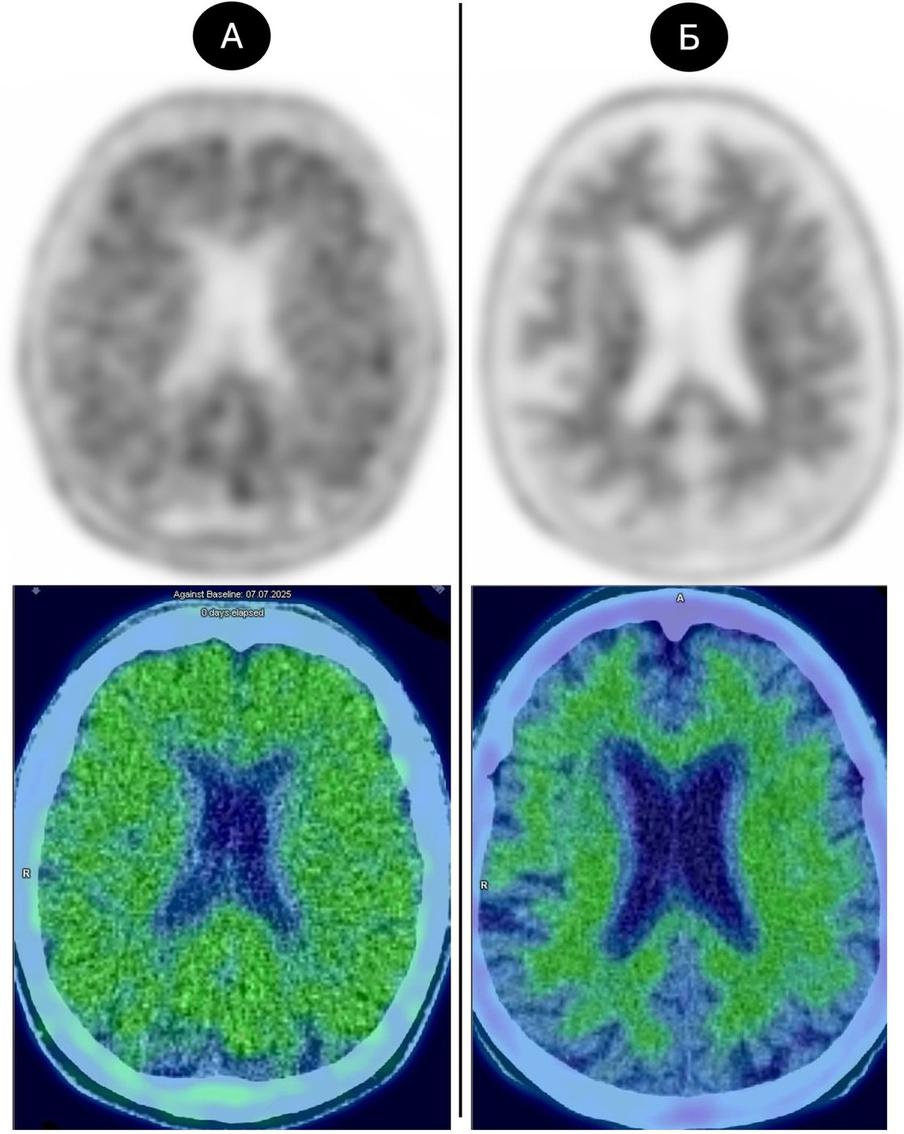

Метод позиционно-эмиссионной томографии (ПЭТ) – менее инвазивный. Чаще всего его используют в онкологии, поэтому научная работа центра проходит в сотрудничестве с ФГБУ “НМИЦ онкологии им. Н. Н. Блохина”, где есть необходимый аппарат.

– До процедуры пациенту внутривенно вводят специфический радиофармацевтический лекарственный препарат, который при патологических отложениях бета-амилоидов в головном мозге напрямую связывается с ними. При положительном результате отчётливо видно лекарство, которое таргетно попадает именно в поражённые участки. На основании этого результата может быть диагностирована болезнь Альцгеймера.